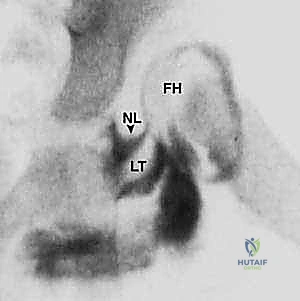

يُعد الخلع الوركي التطوري (Developmental Dysplasia of the Hip - DDH) من أكثر التشوهات الهيكلية شيوعاً التي تؤثر على نمو مفصل الورك لدى الأطفال. المفصل الطبيعي للورك هو مفصل من نوع "الكرة والتجويف" (Ball and Socket). الكرة هي رأس عظم الفخذ (Femoral Head)، والتجويف هو الحُق (Acetabulum) الموجود في عظم الحوض.

- الأشعة السينية (X-rays): تُستخدم للأطفال الأكبر من 6 أشهر بعد بدء تعظم رأس الفخذ.

6. التصوير الإشعاعي داخل العمليات:

خلال جميع هذه الخطوات، يتم استخدام جهاز الأشعة السينية المحمول (C-arm) للتأكد من أن المفصل في وضعه المثالي والتشريحي بنسبة 100%.

صور إضافية لخطوات الجراحة الدقيقة والمتابعة الإشعاعية

يوثق الأستاذ الدكتور محمد هطيف كل خطوة جراحية لضمان أعلى معايير الجودة والشفافية الطبية.